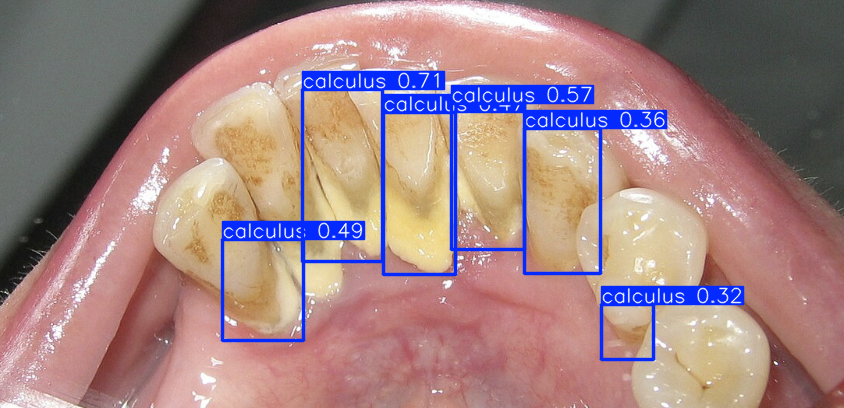

We trained a Computer Vision model on 10,000+ human-labeled dental images from Roboflow using Amazon SageMaker Studio. Our model classifies oral diseases such as ulcers, hypodontia, gum inflammation, caries, calculus, and tooth discoloration.

Successfully trained a Computer Vision AI model capable of detecting oral diseases such as cavities, gingivitis, and tooth discoloration from image data. Built a functional interface for patients to upload photos and receive clear, visualized results, making AI-powered diagnostics more accessible. Managed to create a pipeline that connects AI, cloud tools, and authentication systems — even if not fully deployed, the architecture is in place for future completion.